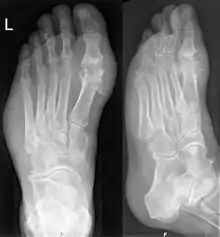

يمكن تشخيص وعلاج النِقْرس بدون الحاجة لمزيد من الفحوصات إذا كان المريض مصاب بفرط حمض البول في الدم ونِقْرس إبهام القدم. وينبغي إجراء تحليل السائل الزلالي إذا لم يكن التشخيص مؤكداً.[3] ورغم الفائدة العائدة من استخدام الأشعة السينية للتعرف على الإصابة المزمنة بالنِقْرس، إلا أنها قليلة النفع في الإصابات الحادة.[9]